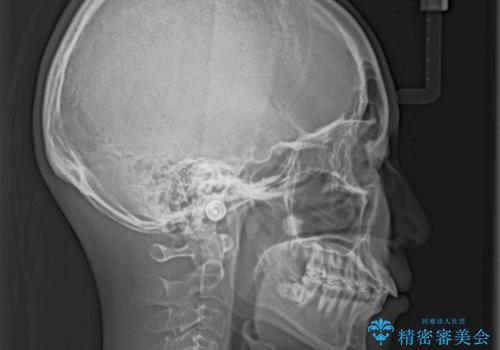

- 上の前歯の出っ歯を治したいとのことで来院された患者様です。

上下顎ともにIPR(歯と歯の間を削る)と歯列全体の拡大によって口元が引っ込むように設計し、インビザラインにより治療を行うこととしました。